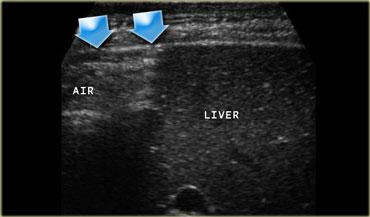

(Tiếp theo) Hình bên trái là một hình ảnh khác của bệnh nhân bị thủng loét tá tràng.

Ở tư thế nằm nghiêng trái, có thể thấy khí tự do tập trung giữa gan và thành bụng bên.

Trong loét dạ dày – tá tràng, siêu âm hiển thị hình ảnh dày thành tá tràng không đối xứng, trong đó có cấu hình khí cố định kéo dài từ lòng tá tràng đến ngoại vi thành hoặc thậm chí xâm nhập vào lớp mỡ viêm lân cận.

Tư thế nằm nghiêng phải sẽ cho phép dịch dạ dày – thường hiện diện trong bệnh loét dạ dày – tá tràng – di chuyển xuống tá tràng, giúp quan sát ổ loét rõ hơn.

Trong trường hợp thủng, có thể phát hiện đường dẫn khí từ ổ loét vào khoang phúc mạc, thường theo hướng bụng hoặc đầu.

Khí tự do được hiển thị rõ nhất ở tư thế nằm nghiêng trái, nằm giữa gan và thành bụng phải.